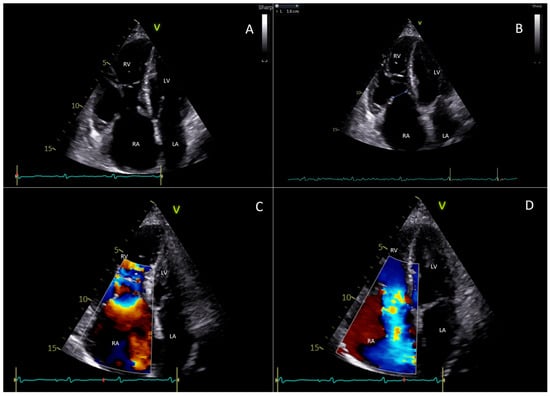

- Cammalleri, V.; Piscione, M.; De Luca, V.M.; Antonelli, G.; Cocco, N.; Nusca, A.; Gaudio, D.; Nobile, E.; Coletti, F.; Bianchi, A.; et al. Carcinoid Pulmonary Valve Stenosis: Multimodality Imaging and Transcatheter Valve Implant with Prestenting Technique. Circ. Cardiovasc. Imaging 2024, 18, e016785. [Google Scholar] [CrossRef] [PubMed]